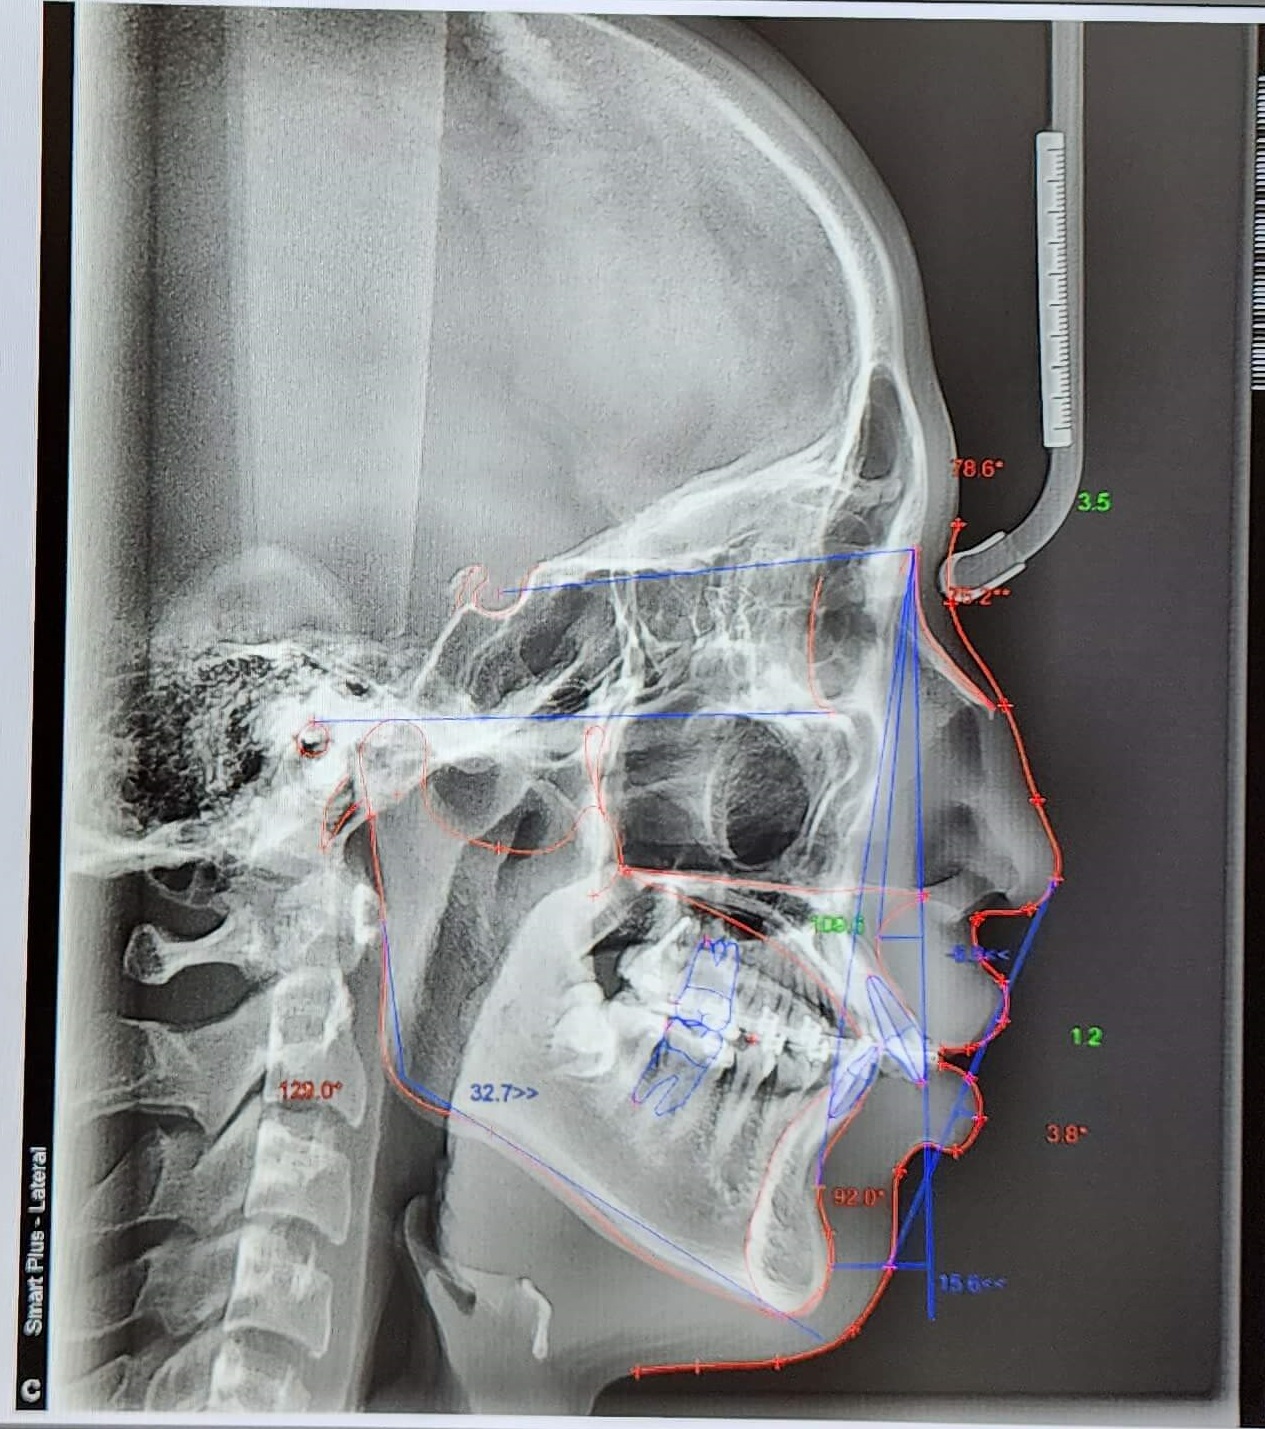

전체적인 치아상태 및 배열 안면윤곽 상태 등 정밀검사를 실시하였으며 아들이 고등학생이어서 성장판 검사는 별도로 하지 않았습니다.

정밀검사비용은 150,000원이 들었으며 전체교정비용은 590만 원으로 결정이 되었습니다. 치료방법에 따라 다르기 때문에 참고만 하시길 바랍니다.

● 검사결과 내용

치아뿌리상태는 좋고 어금니 가위교합(3개월정도)을 먼저 하고 어느 정도 진행이 되면 전체브라켓을 설치 후 과개교합(2개월정도) 교정을 실시한후 2차 정밀검사를 하고 발치여부를 판단하기로 하였습니다.

저는 상담 시 되도록이면 발치는 하지 않는 방향으로 한다고 말씀드렸고 다행히 2차 정밀검사 마친 후 발치 없이 전체교정을 시작할 수 있었습니다.

▼ 1차 정밀 검사 X-RAY

▼ 치아상태 및 얼굴 각도 치아 치수확인